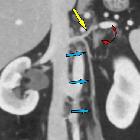

- the left gonadal vein drains into the left renal vein

- the right gonadal vein drains directly into the inferior vena cava

The right ovarian vein arises from the right pampiniform plexus (which is continuous with the uterine plexus) and lies lateral to the right ureter. It ascends anterior to psoas and parallels the right ureter. It crosses the ureter anteromedially halfway between bifurcation of the IVC and the point in which it joins the anterolateral inferior vena cava (IVC).

The left ovarian vein ascends similarly into the abdomen but drains into the left renal vein .

The testicular vein ascends in the retroperitoneum on psoas major. Along its course there are variable communications with retroperitoneal veins, abdominal wall veins and renal capsular veins. The left testicular vein invariably drains into the left renal vein. The right testicular vein usually drains into the IVC just below the renal vein, but sometimes drains into the right renal vein.